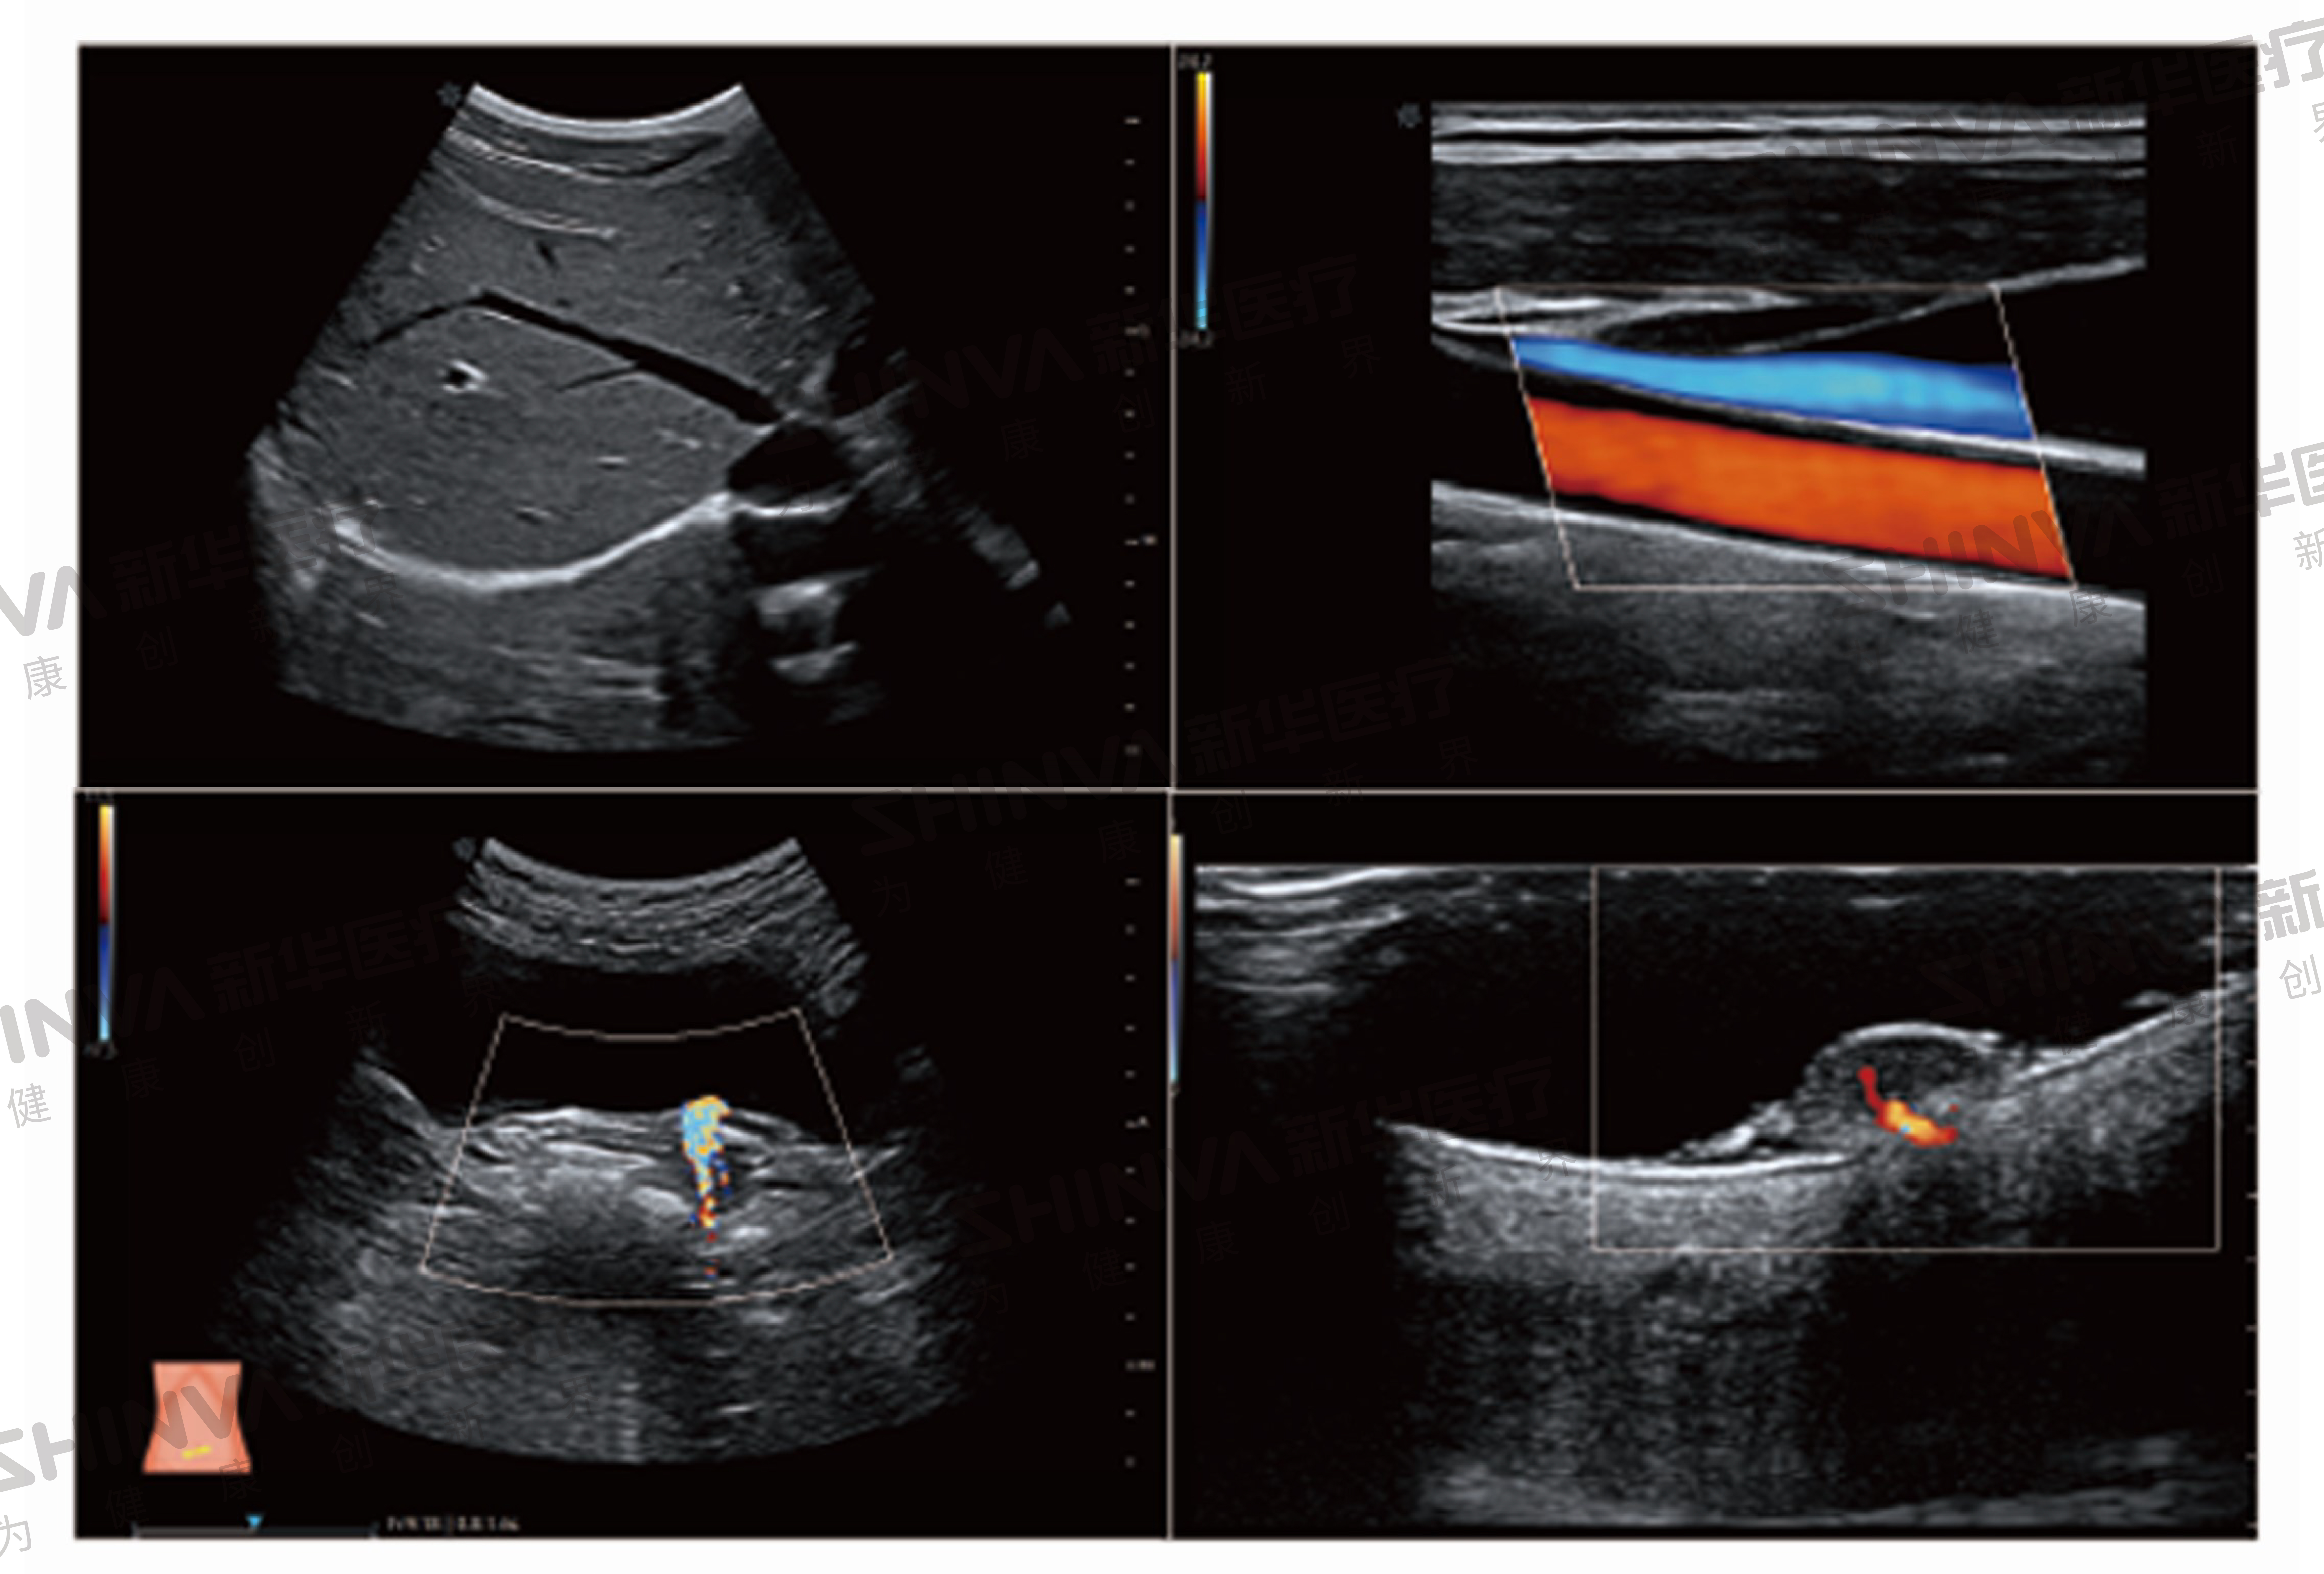

系统搭载全新单晶体探头及高端成像技术,轻松获得更高质量的图像。系统采用最先进的发射接收技术,保证图像整场均一性的同时,大幅提升图像的分辨率、穿透力和高端应用性能,助力临床疑难病例的诊断教学。

智能应用:智能产科分析、NT自动测量、甲状腺实时智能分析、乳腺实智能分析、小儿髋关节半自动测量、心功能自动分析、智能血管应用成像、智能多普勒